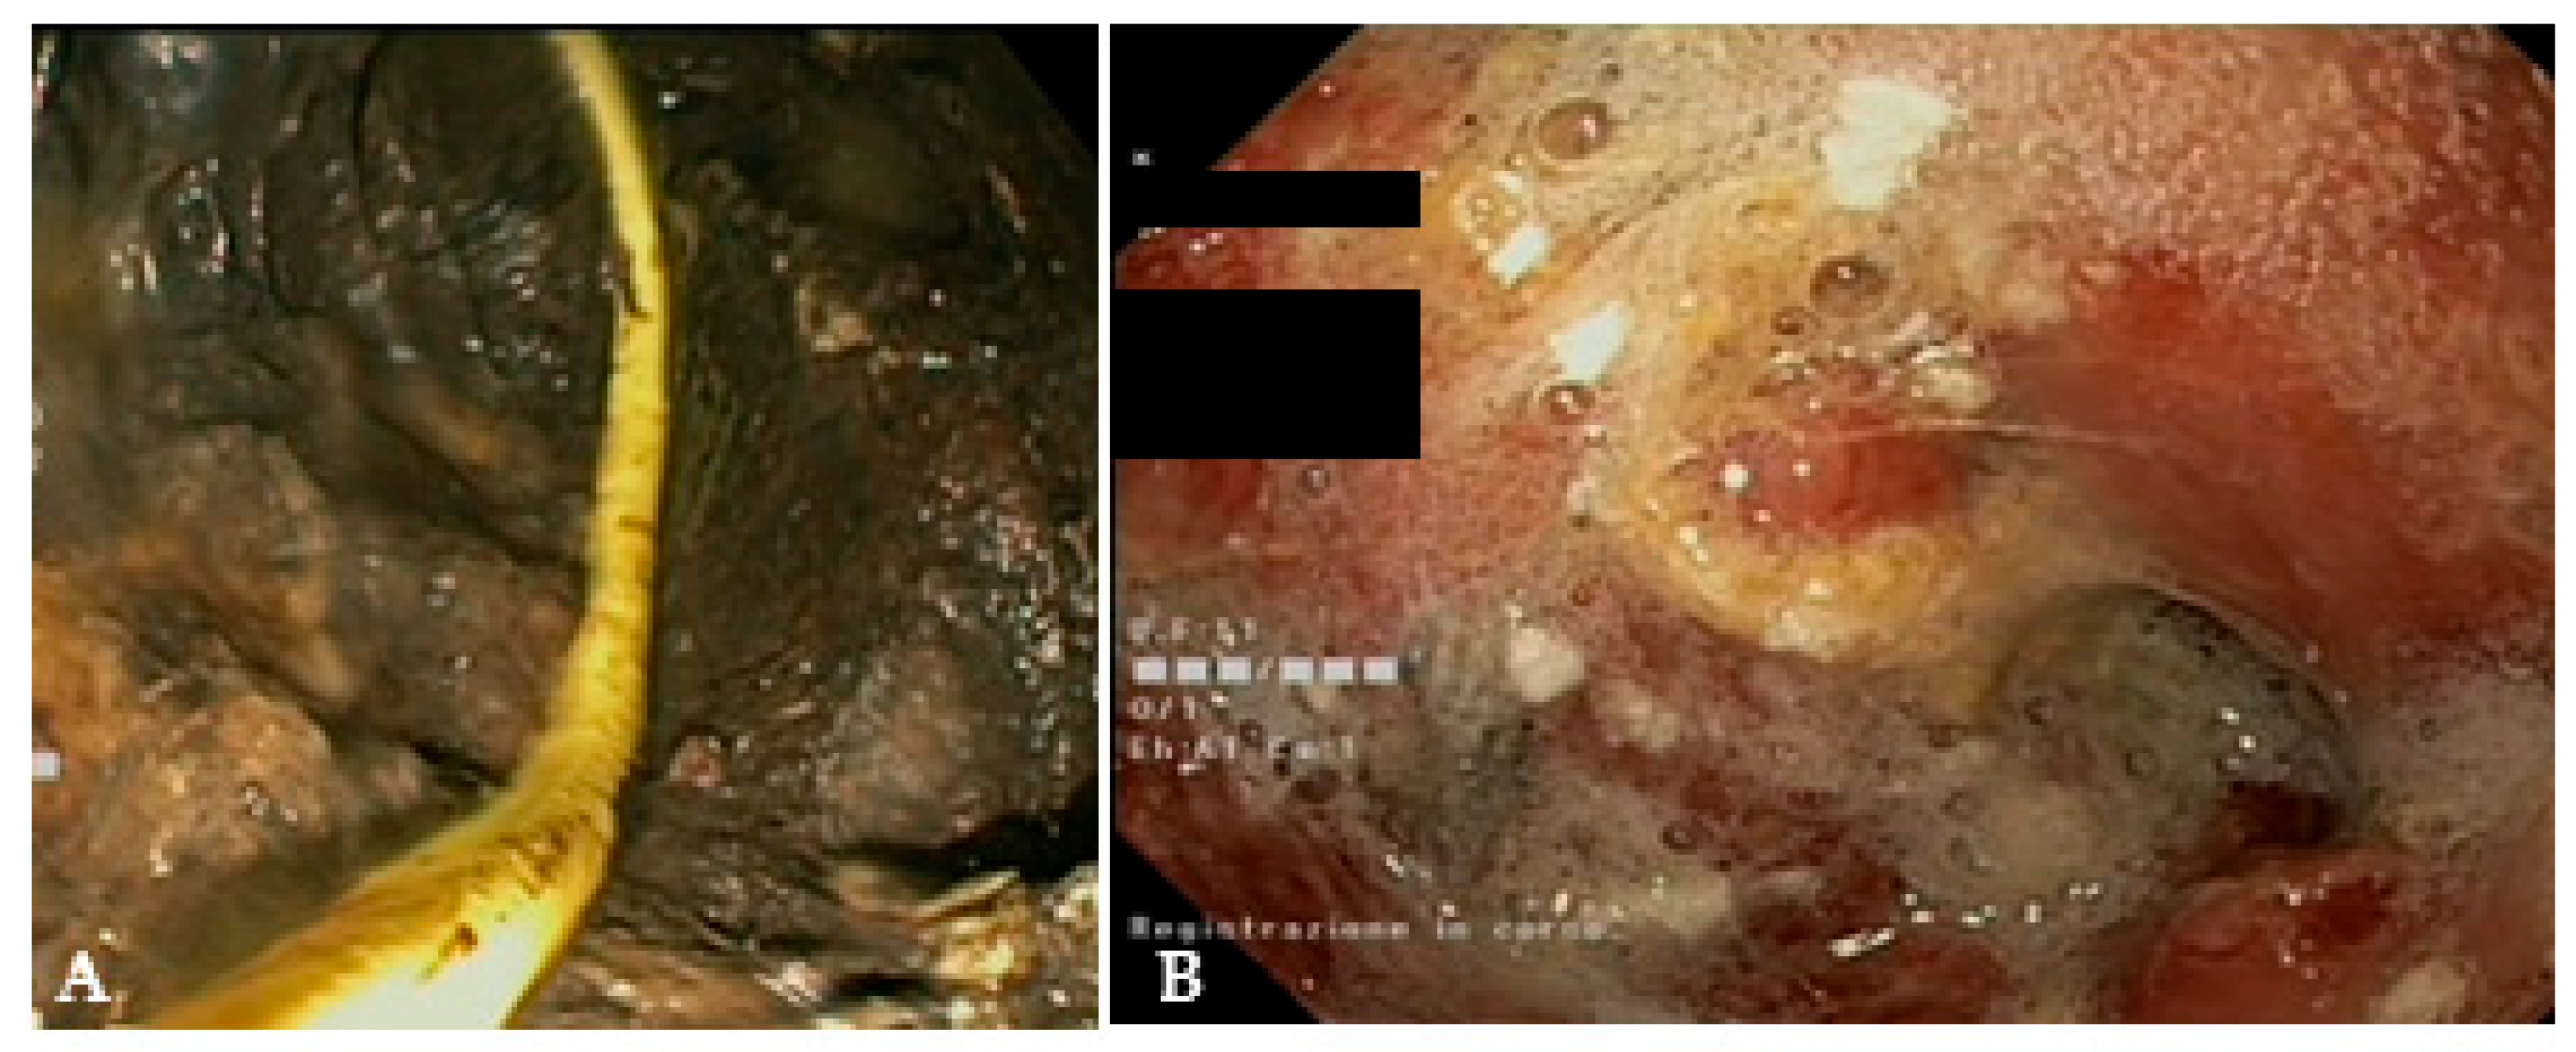

Figure 6.

(A) Endoscopic view of a naso-cystic catheter within a necrotic collection; (B) endoscopic view of a retroperitoneal cavity after lavage with peroxide hydrogen.